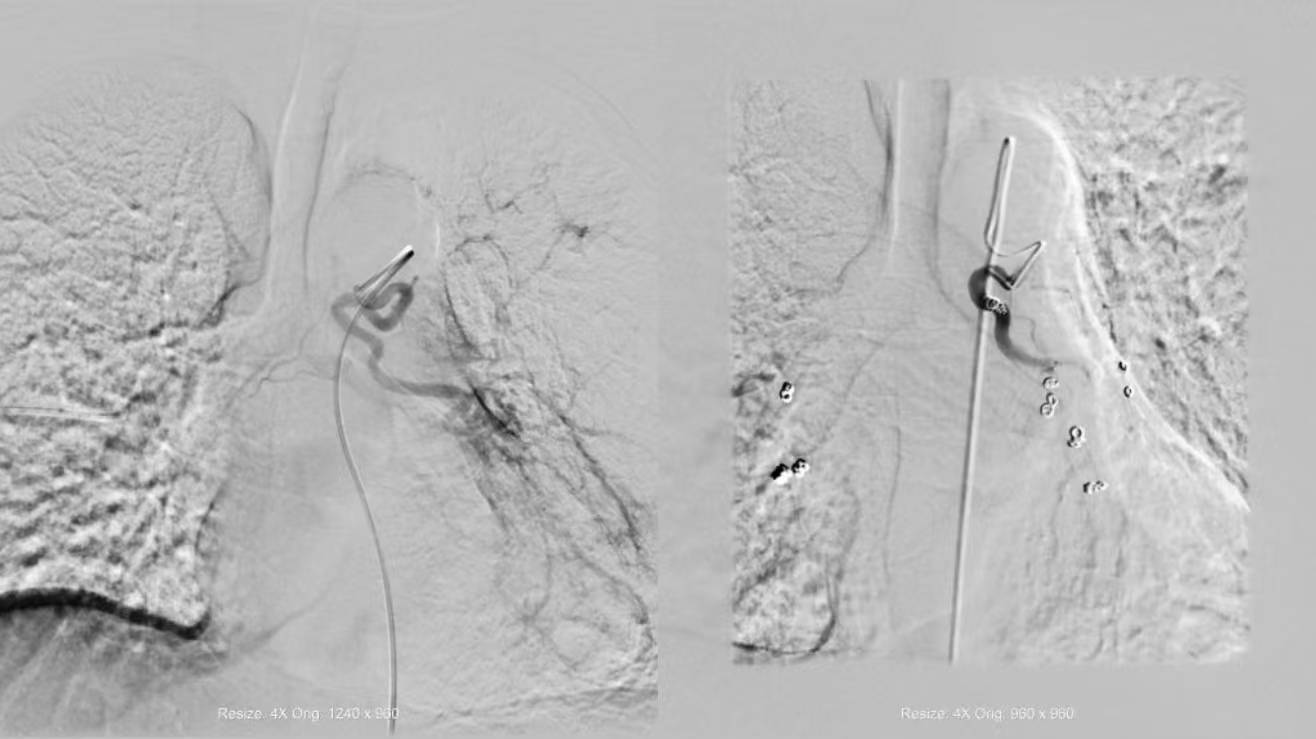

配准 超选

栓塞+超选 栓塞

术前CTA与术中DSA影像精准配准,3D Fusion技术让迂曲血管立体呈现,Overlay技术将血管走形叠加在实时画面上——原本“盲探”的出血点,瞬间“一眼锁定”。微导管在导航引导下快速且精准到达靶血管,快速注入栓塞剂顺利止血。从麻醉到手术结束,仅用45分钟,较传统手术缩短近2小时。